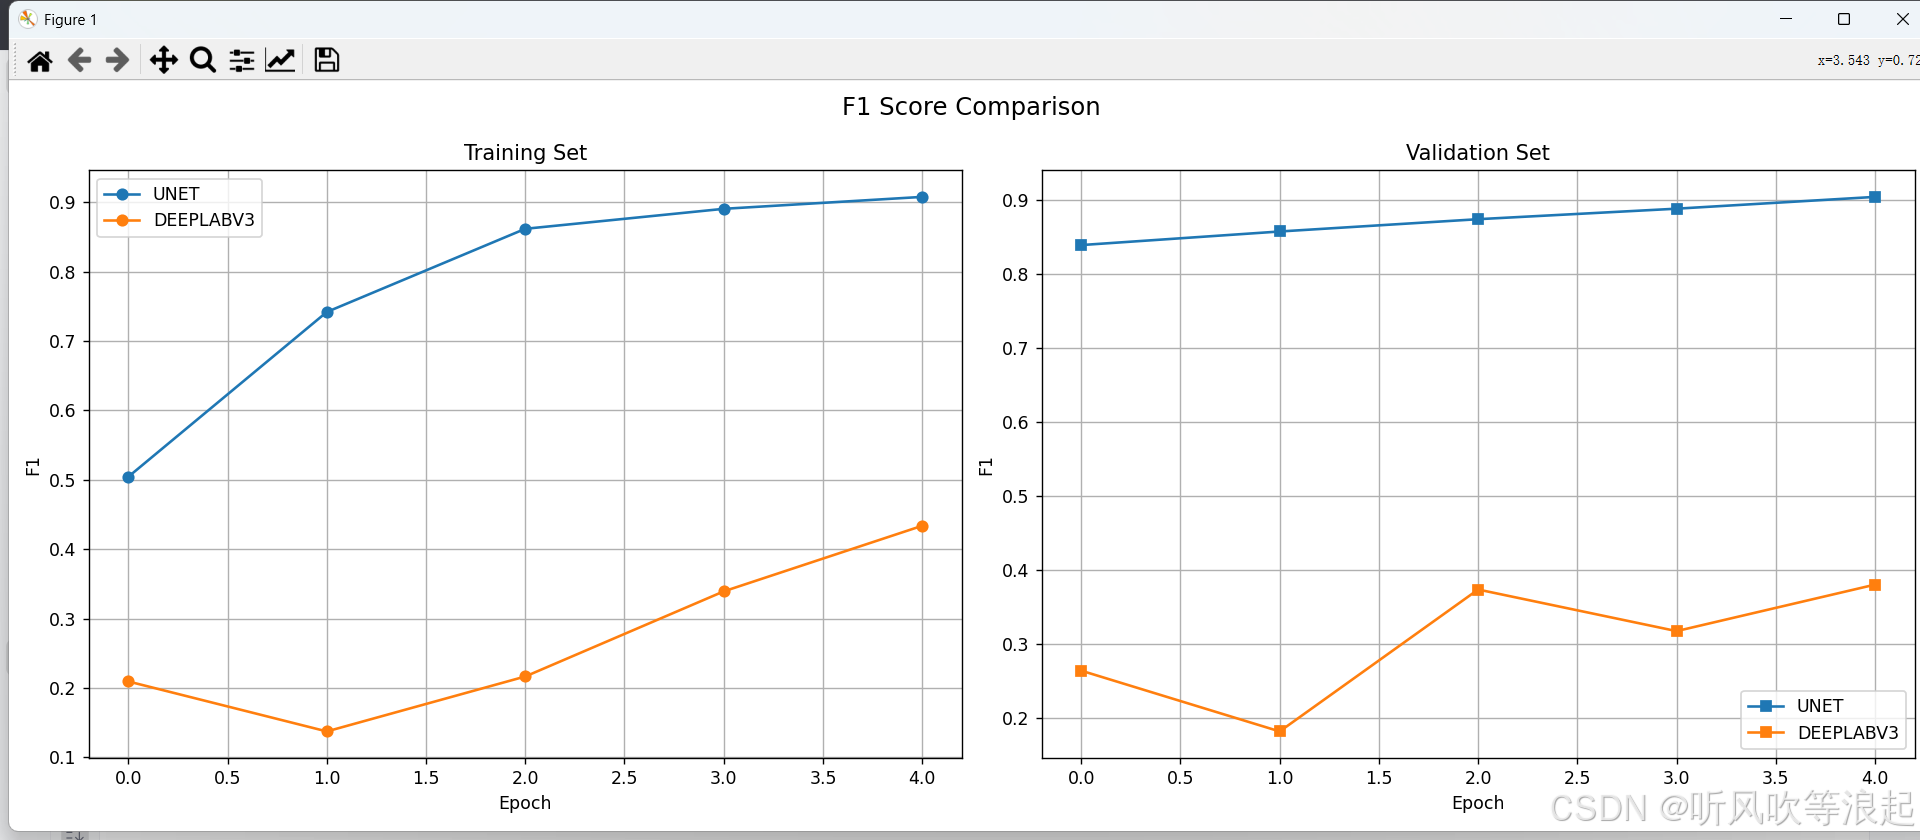

scheduler = lr_scheduler.LambdaLR(optimizer, lr_lambda=lf)4.模型对比分析

通过可视化工具可以直观比较不同模型的性能表现:

ax2.plot(epochs, values, label=model_name.upper())可视化结果通常显示:

- UNet在小数据集上通常收敛更快

- DeepLabV3在大数据集上表现更优

- 两种模型在不同指标上的曲线

这里仅仅训练了5个epoch用于测试代码的可行性,指标不做参考

3.对比